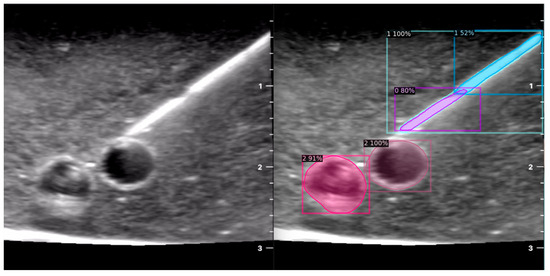

When the model is applied, the original ultrasound image is overlaid with a new layer that presents the detection results, offering insights into predicted target areas (Figure 4 and Figure 5).

The segmentation area represents the region identified by the model as each object class (needle tip, needle body, blood vessel, or nerve bundle). This area is visually highlighted, allowing for a clear understanding of what structure is of interest. To provide additional context, a bounding box in the shape of a square is placed around the segmentation area, enclosing the detected object and providing a concise representation of its location. These are illustrated in Figure 4, Figure 5 and Figure 6, with original images on the left and overlayed images on the right for our three different phantom models.

In order to assess the confidence level of the model’s predictions, a confidence percentage is assigned for each object class labelled (Figure 4, Figure 5 and Figure 6). This percentage represents the probability of a true positive detection by the model. It quantifies the model’s level of certainty regarding the accuracy of its prediction for each detected defect.

Figure 4. Model inference in Phantom A (Agar 2.5% with septanol and psyllium husk).